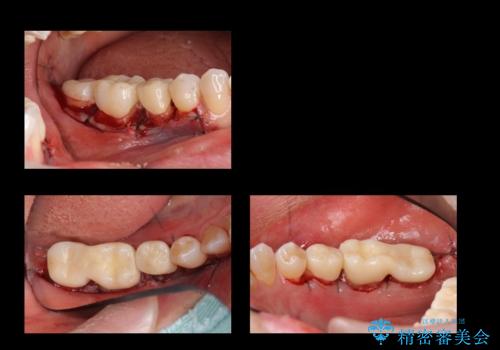

- 右下奥歯(7番)の高さがなく、かぶせ物(クラウン)にするためにあらかじめ歯周外科手術を行いました。(クラウンレングスニング)

右下5番は歯ぐき付近までWSD(くさび状欠損)で削れていたため、患者様と相談してクラウンにしました。その際、削れていたのが歯肉縁下に及んでいたため、一緒に手術範囲に含めました。

- 外科手術のため、術後に出血、痛みや腫れ、違和感を伴います

- 口腔内の状態によっては適応できないことがあります